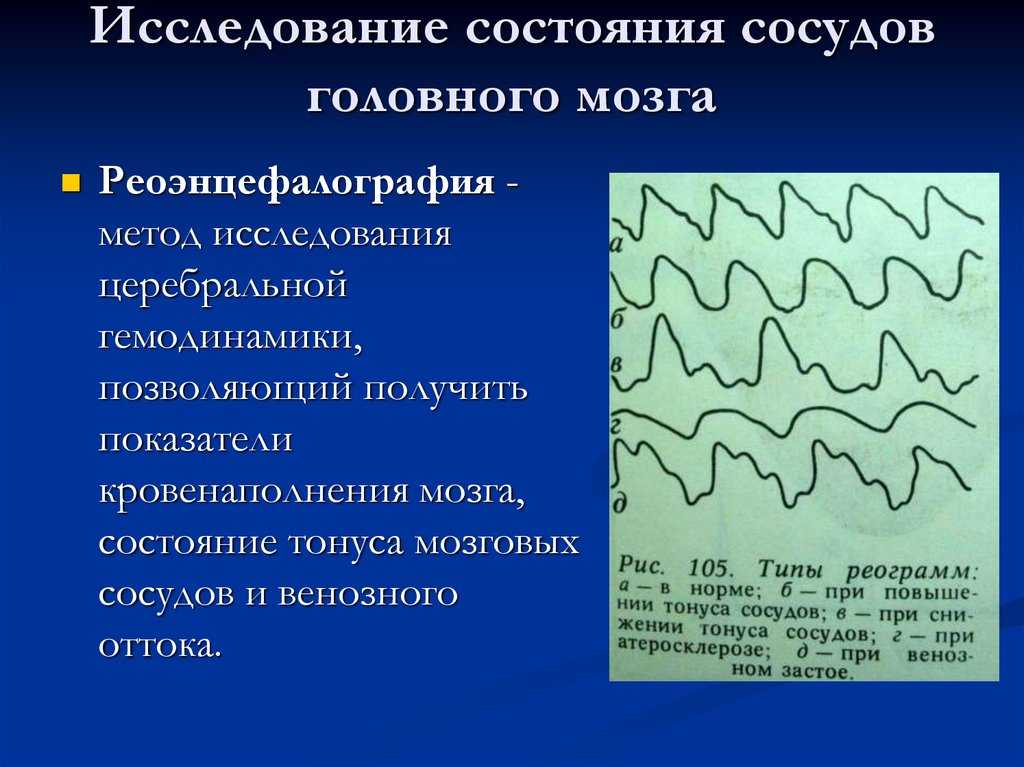

Как провести проверку состояния сосудов головного мозга дома?

Узнайте, как самостоятельно оценить состояние сосудов вашего головного мозга, не выходя из дома, с помощью простых и доступных методов проверки.